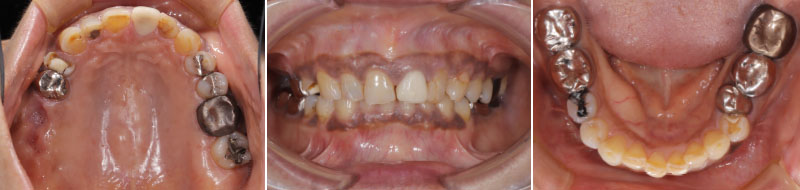

- こちらで、当院の治療フローをご説明させて頂く症例のBasic Dataは、以下となります -

主訴:前歯を綺麗にして欲しい

希望:セラミック治療を希望

年齢:60歳

性別:女性

既往歴:なし

喫煙:2年前まで喫煙歴あり

飲酒:しない

受診歴:1年ぶりの歯科医院受診

まずは、患者様の「現状の把握」から始めます。資料収集を正確に行うことにより、正確な診断が可能となり、現状の状態になっている原因を知ることができます。資料収集は歯だけではなく、多角的に顔貌から口元も含めトータル的に行います。

尚、こちらに掲載している写真や画像等は、それら資料収集の内容の1部です。皆様に視覚的にご理解頂きやすい資料のみ掲載しております。

以下症例ですが、写真を見て頂ければわかるように、赤唇部分が薄く、口角の上がり方に左右差あることがわかります。単純に歯を治療するだけでは、この状態を正常な形に整えることはできません。

また、噛み合わせにも問題があり、1部の歯は歯茎が下がっていることも分かって頂けると思います。